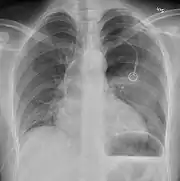

Chest tube

A chest tube placed on the right for a pneumothorax

A chest tube (or intercostal drain) is the most definitive initial treatment of a pneumothorax. These are typically inserted in an area under the axilla (armpit) called the "safe triangle", where damage to internal organs can be avoided; this is delineated by a horizontal line at the level of the nipple and two muscles of the chest wall (latissimus dorsi and pectoralis major). Local anesthetic is applied. Two types of tubes may be used. In spontaneous pneumothorax, small-bore (smaller than 14 F, 4.7 mm diameter) tubes may be inserted by the Seldinger technique, and larger tubes do not have an advantage.[15][47] In traumatic pneumothorax, larger tubes (28 F, 9.3 mm) are used.[41] When chest tubes are placed due to either blunt or penetrating trauma, antibiotics decrease the risks of infectious complications.[48]

Chest tubes are required in PSPs that have not responded to needle aspiration, in large SSPs (>50%), and in cases of tension pneumothorax. They are connected to a one-way valve system that allows air to escape, but not to re-enter, the chest. This may include a bottle with water that functions like a water seal, or a Heimlich valve. They are not normally connected to a negative pressure circuit, as this would result in rapid re-expansion of the lung and a risk of pulmonary edema ("re-expansion pulmonary edema"). The tube is left in place until no air is seen to escape from it for a period of time, and X-rays confirm re-expansion of the lung.[15][19][33]